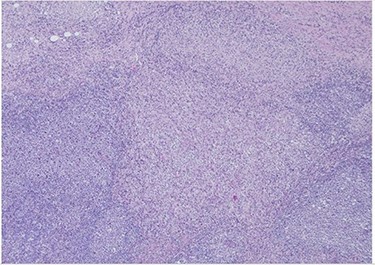

H&E slide (low magnification, 4×) shows characteristic paracortical zonal process involving part of a lymph node. Background consists of preserved nodal architecture with a follicular center and a mantle zone adjacent to intervening pale areas.